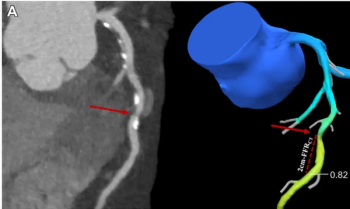

In nearly 5,300 patients with suspected coronary artery disease (CAD), adjunctive use of CT-based fractional flow reserve software significantly reduced the 90-day invasive coronary angiography (ICA) rate in comparison to unassisted use of coronary computed tomography angiography (CCTA).